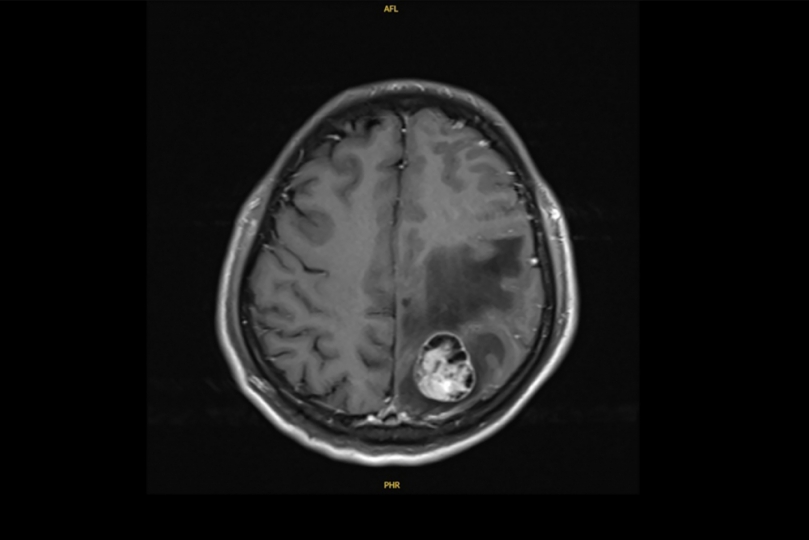

彰基醫學中心曾於3年前成功治癒一名合併腦轉移的肺腺癌個案,透過跨科團隊精準治療,病人終於康復重返職場,彰基說,患者是41歲許姓男子,從事文具業務,為家裡經濟支柱,三年前(2022年)6月某日清晨,右側肢體突然無力、抽搐,繼而倒地不起,許男由家人送彰基急診,經電腦斷層和核磁共振檢查,發現腦部有約3.1公分腫瘤,進一步追蹤,右下肺有4公分腫塊,醫師確診肺腺癌合併腦轉移。

林聖皓醫師說,經一段時間影像追蹤,顯示肺部腫瘤從原本的4公分縮小為2.8公分,控制成效顯著,儘管標靶藥物初期控制良好,許姓患者仍出現神經症狀,胸腔內科隨即啟動跨科整合照護,與神經外科孫立偉醫師合作完成腦部腫瘤手術,術後雖神經功能逐漸恢復,但考量治療效果,經與胸腔外科召開跨科討論後,由洪維亨醫師進行「肺葉切除」手術,達成更徹底控制。